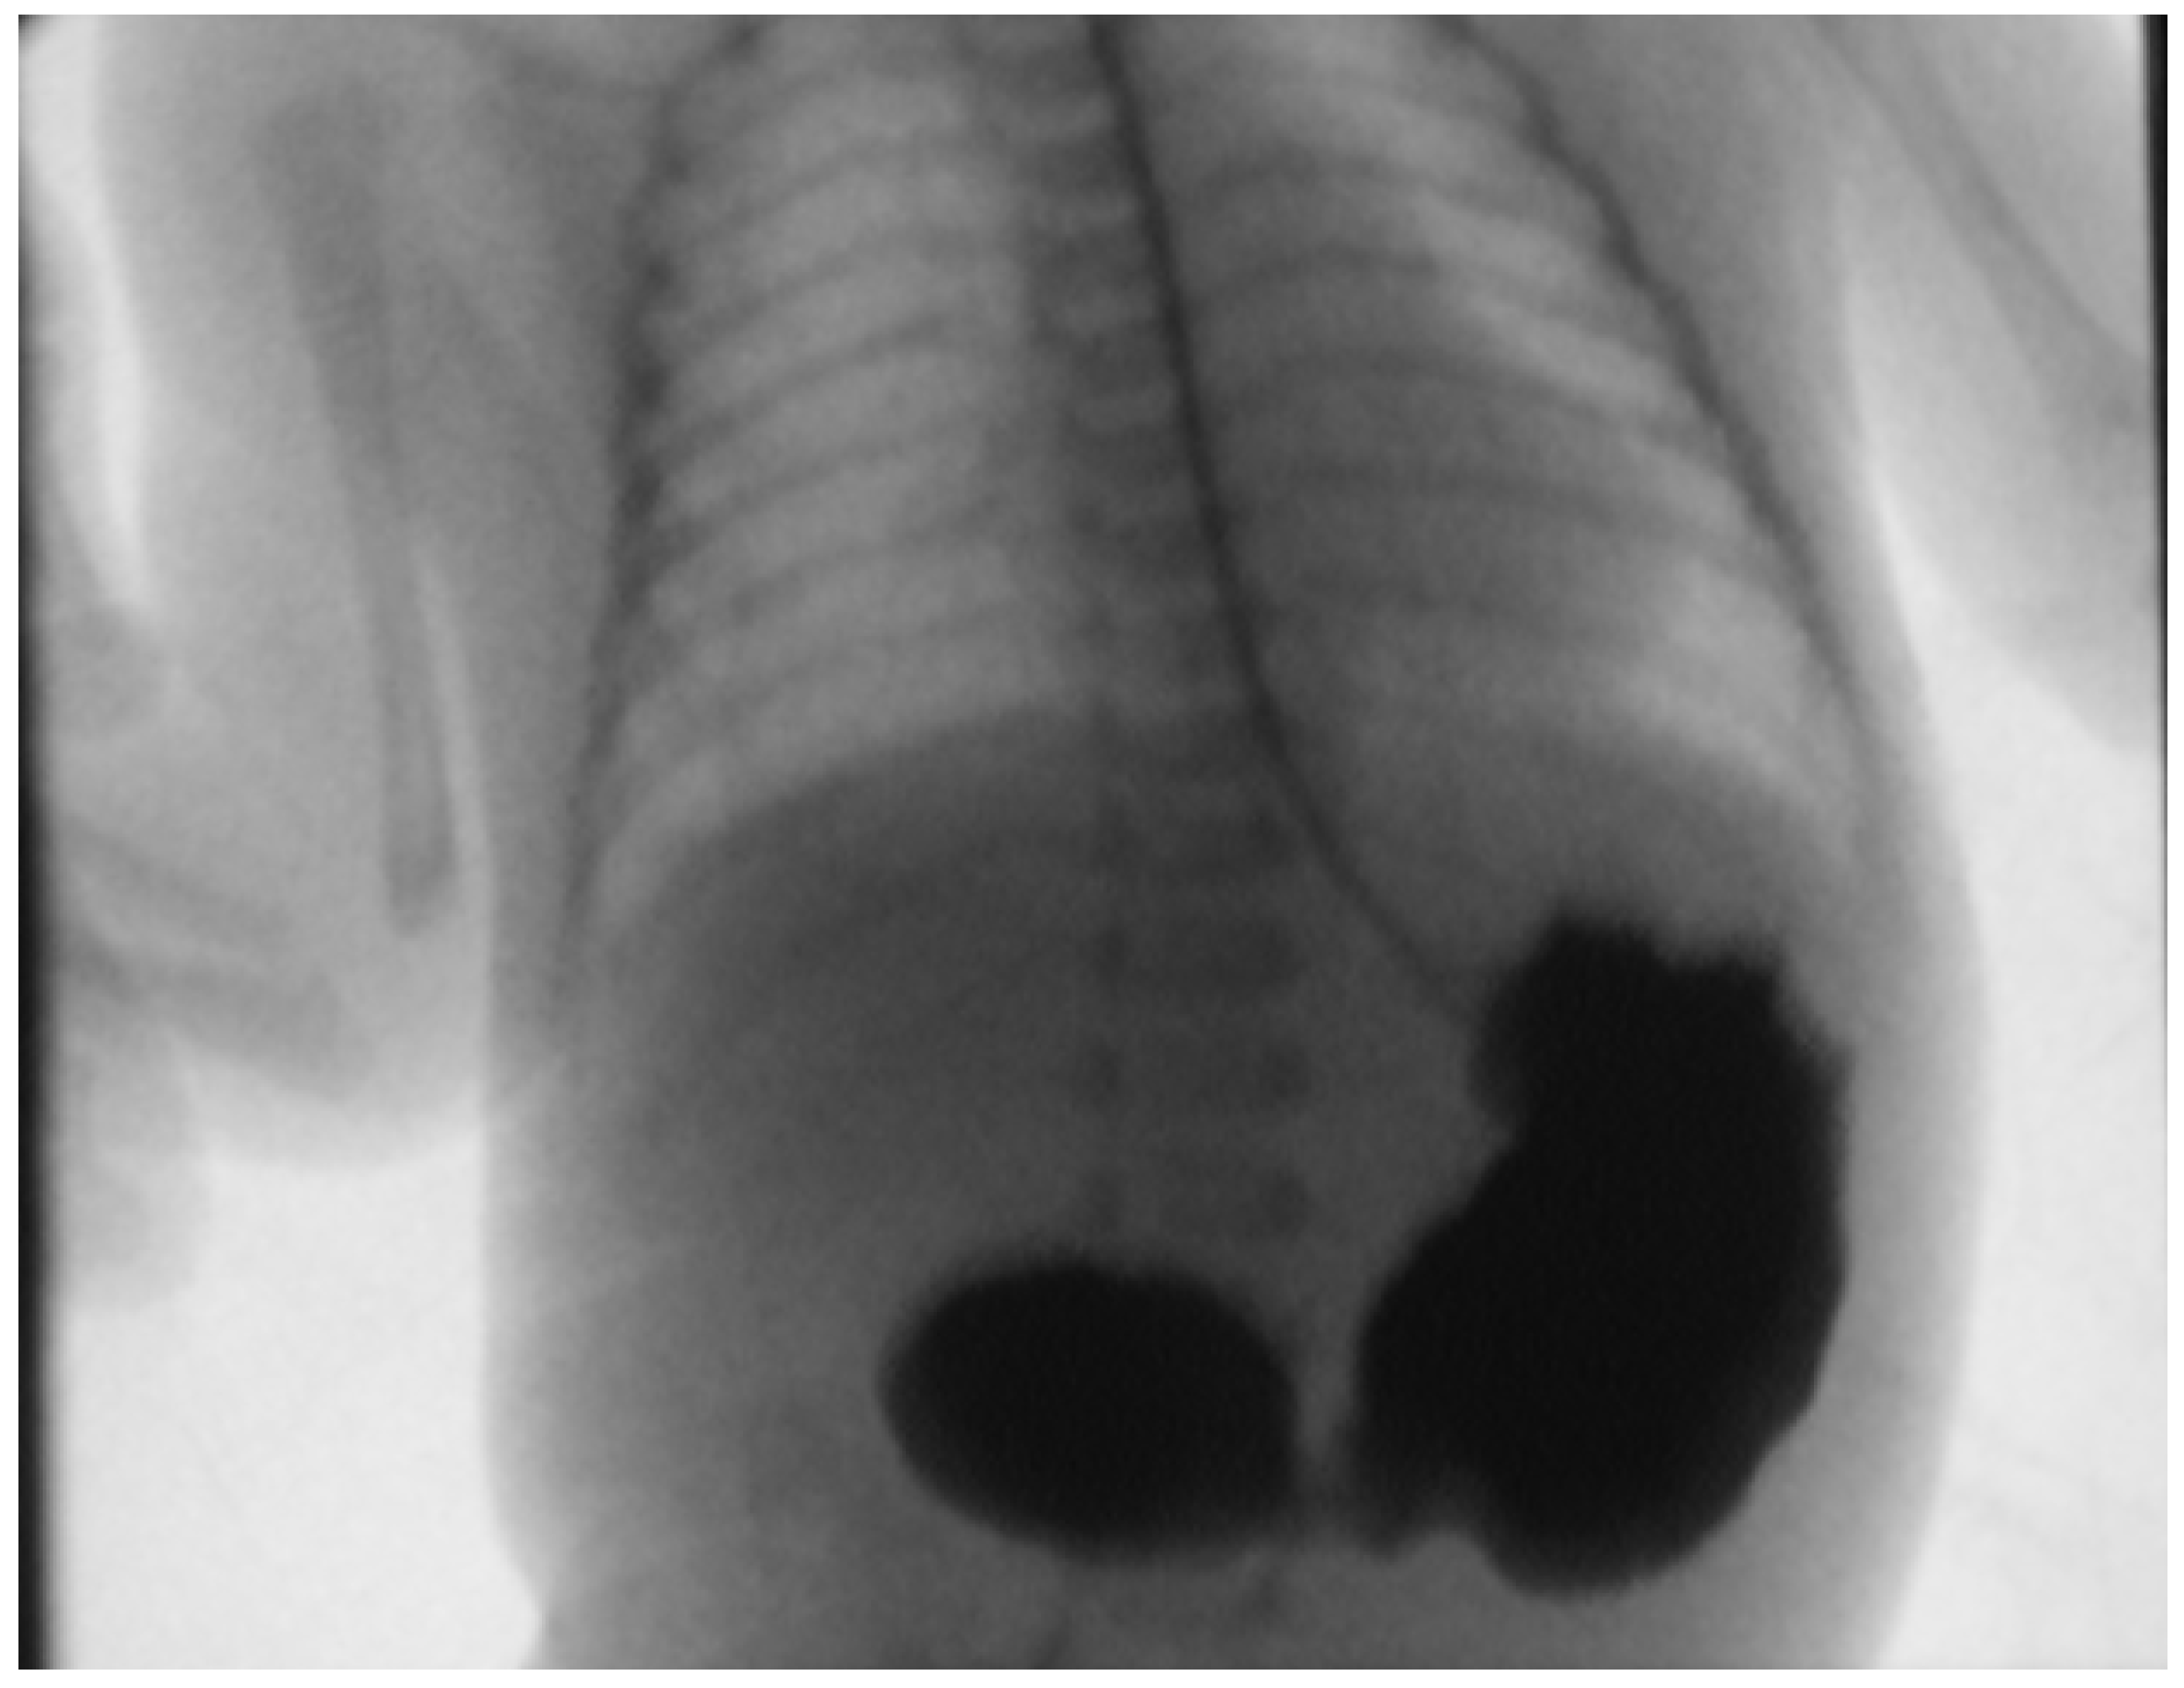

- Koberlein, G.; DiSantis, D. The “double bubble” sign. Abdom. Imaging 2016, 41, 334–335. [Google Scholar] [CrossRef] [PubMed]

- Traubici, J. The Double Bubble Sign. Radiology 2001, 220, 463–464. [Google Scholar] [CrossRef] [PubMed]